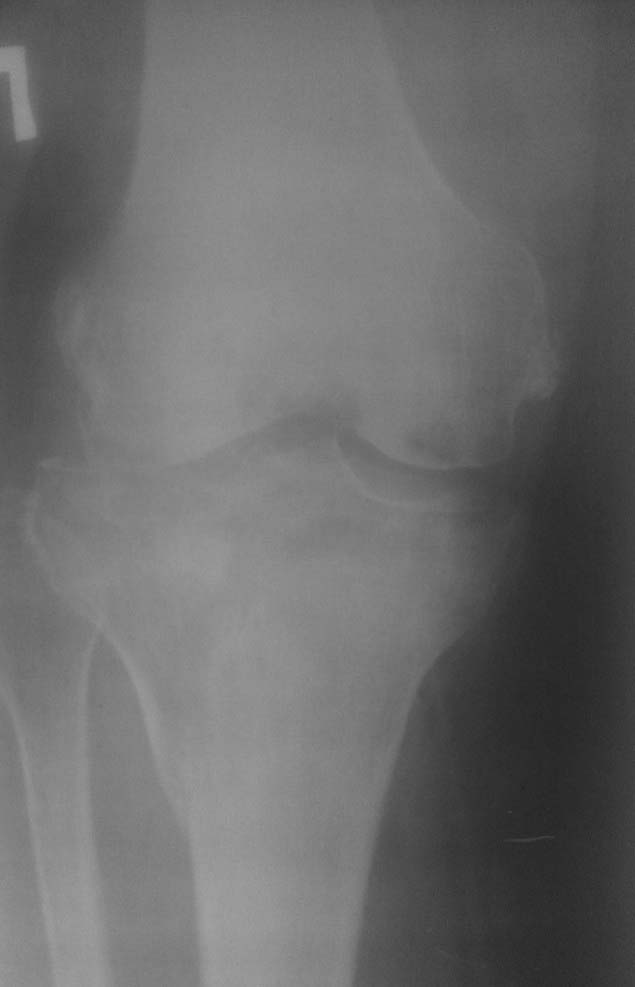

Травма от июля 2011 года, лечили консервативно гипсовым тутором (про травму лодыжек - не помнит или не знает). Через 2 недели после травмы - легочная эмболия и илеофеморальный тромбоз, находился на стац лечении. После теоретического сращения мыщелков и снятия гипсового тутора разработка движений безрезультативна, опорности конечности нет. Со слов - прыгает на костылях до самого настоящего момента.Сейчас - боль, передний ящик, люфт при нагрузке на ВБС. Боль в области внутренней лодыжки. Движения в голеностопе 5-0-15, в коленном суставе - 0-0-10, болезненные. При попытке встать полным весом и сделать шаг - нестабильность, ногу подворачивает.Ваши предложения?Пациент просит опорной ноги, сам вроде как активный (хотя толком объяснить, чем он занимался целый год, не может..)С Уважением, Останин

Неплохо было бы увидеть КТ мыщелков или рентгенограммы;) Что означает нестабильность при попытке сделать шаг? Передний ящик -сомнительно при таком объеме движений. Люфт и ногу подворачивает - а что люфтит? и куда он ее подворачивает (похоже больше чем на сгибание)? Если речь идет о вальгусном отклонении, то следует разделить: вальгус от импрессии, вальгус от боковой связочной нестабильности или повреждено и то и другое? Не совсем понятно где болевой синдром более выраженный? Если больной не может понять где болит больше - я бы шел от переферии к центру (плюс к тому, на моем нечетком мониторе голеностоп выглядит хуже).